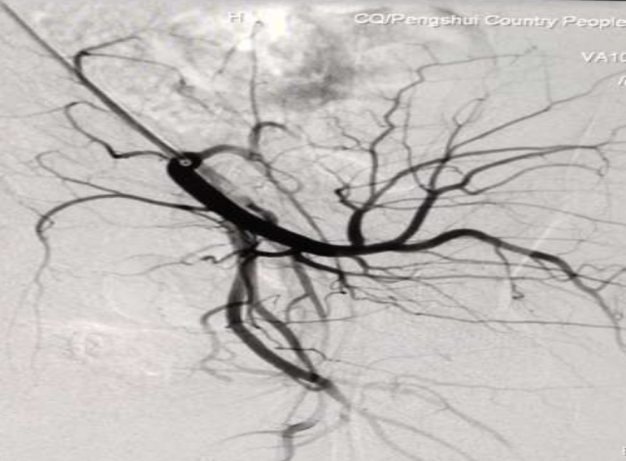

2020年4月26日星期日上午,我院成功完成首例子宫动脉介入造影栓塞术。

26日上午10:50,妇产科医生欧春林在支医专家苏江利、孙会东,我院侯兴志、王启伦、廖洪梅和放射医生的协助下,成功完成子宫动脉栓塞术,上午11:50术毕安返病房。目前,术后患者恢复情况良好。